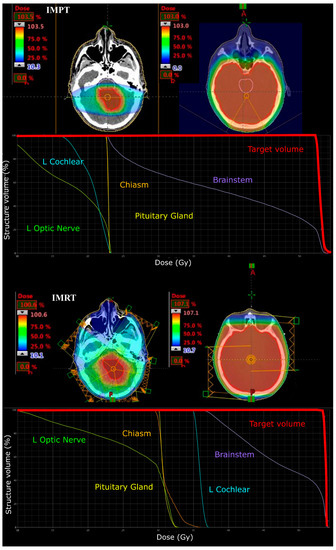

2.2.1. Prescribed Dose and Beam Arrangement for Intensity-Modulated Proton Therapy (IMPT)

2.2.2. Prescribed Dose and Beam Arrangement for Intensity-Modulated Photon Therapy (IMRT)

3.1. Medulloblastoma

3.2. Supratentorial Ependymoma